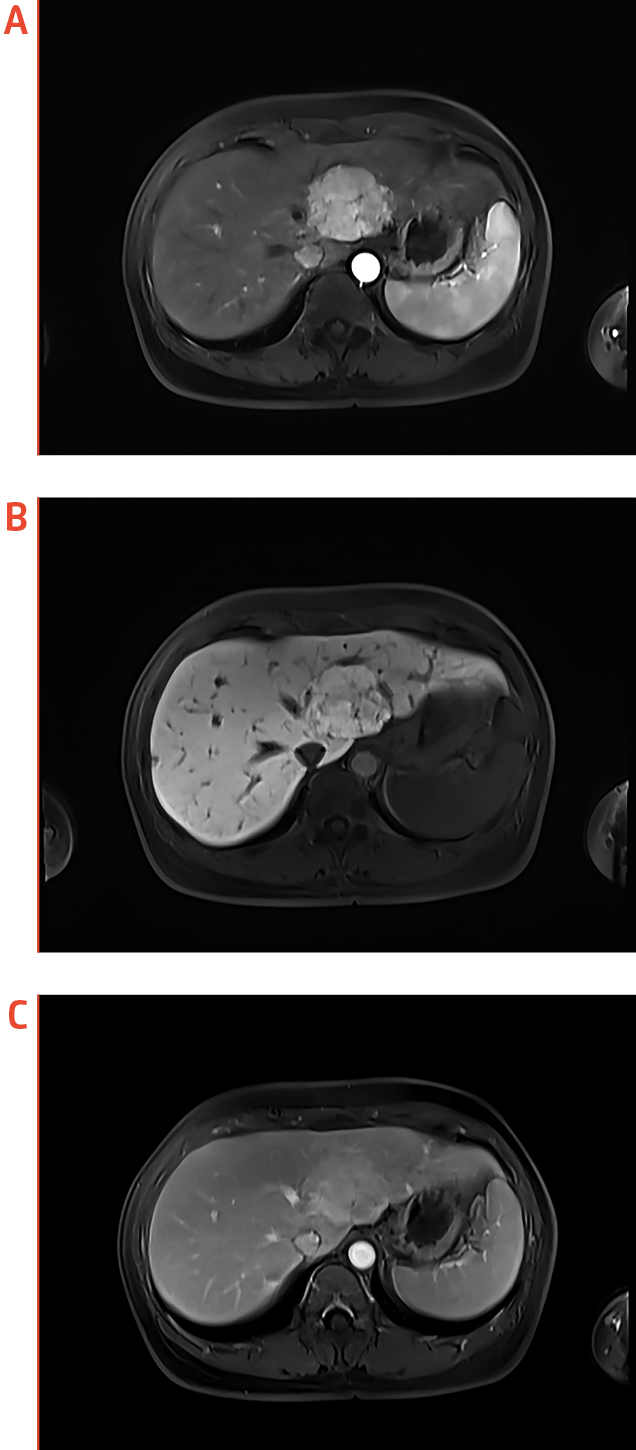

Dr. Ka shared a case of FNH detection, in which a large liver lesion was detected on ultrasound imaging and was worrisome of HCC. The patient was subjected to subsequent EOB-MRI examination. While EOB-modified gadoxetic acid is actively taken up by hepatocytes, HCC lesions do not accumulate gadoxetic acid and thus appear hypointense in the hepatobiliary phase (HBP) as compared to normal liver parenchyma7. In this case, the hepatic lesion shows brisk arterial enhancement as well as gadoxetic acid uptake during HBP (Figure 1b), and hence the lesion was shown to be a FNH.

Figure 1. EOB-MRI identification of a FNH, (a) axial arterial phase, (b) axial HBP, and (c) axial portovenous phase

(images provided by Dr. Ka)